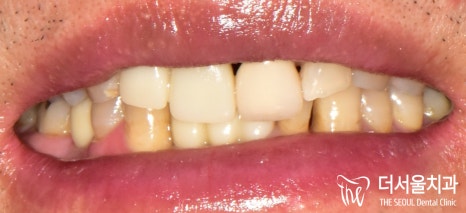

문정동치과 에서

잇몸치료를 병행하며,

임플란트 뼈이식으로

앞니, 어금니 보철 식립을

해드린 결과입니다.

치열이 좀 비뚤어져 있는 것은

아쉽긴 합니다만,

처음 상태와 비교해봤을때,

많이 개선된 것을 확인할 수 있었습니다.

환자분 역시 처음 오셨을때와 달리

몇 년은 더 젊어보인다며,

자신감도 오르고

좋은 결과에 만족하신다며

칭찬을 해주셨습니다.